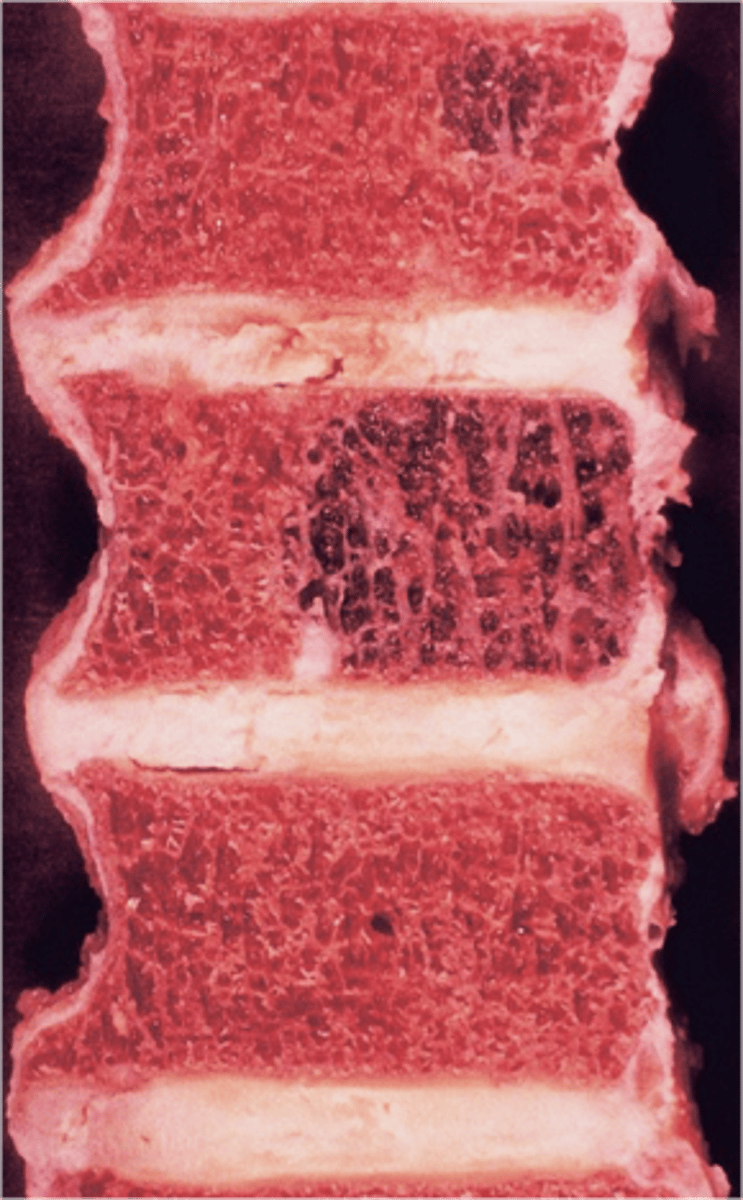

Vertebral hemangioma

- Solitary vascular neoplasm

- Slow growing

- 2-3% of all spine tumors (radiographs)

- 11% of all spines (autopsy)

- Most common benign tumor of the spine

State the incidence of vertebral hemangioma

- First seen over 40 y.o.

- F>M

- Most asymptomatic

- 75% in spine and skull

- Lower thoracic and upper lumbar

- Vertebral body

• Extension into vertebral arch (10-15%)

State the clinical features of vertebral hemangioma

- Vertical striations (corduroy cloth)

- Expansion (rare) may result in neurologic findings

- Skull ("sand dollar")

- Paravertebral swelling

State the radiographic features of vertebral hemangioma

Expansile

_____ vertebral hemangioma

- Left: Paget Disease

- Middle: Vertebral hemangioma

- Right: Osteoporosis

Complete the DDx for vertebral hemangioma